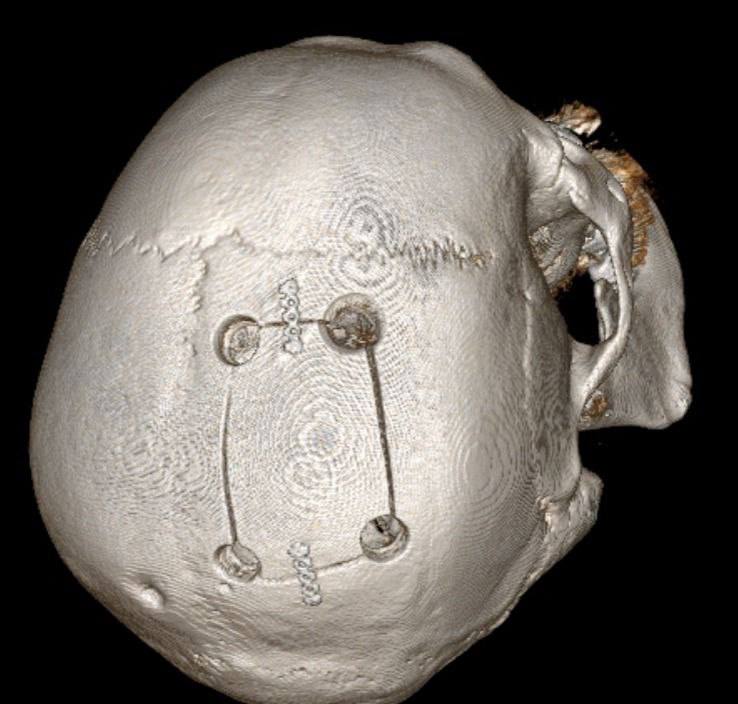

Нейрохирурги провели сложнейшую операцию и полностью удалили опухоль. Несмотря на высокий риск и возраст пациента, вмешательство прошло успешно.

Фото: ГКБ Пятигорска.